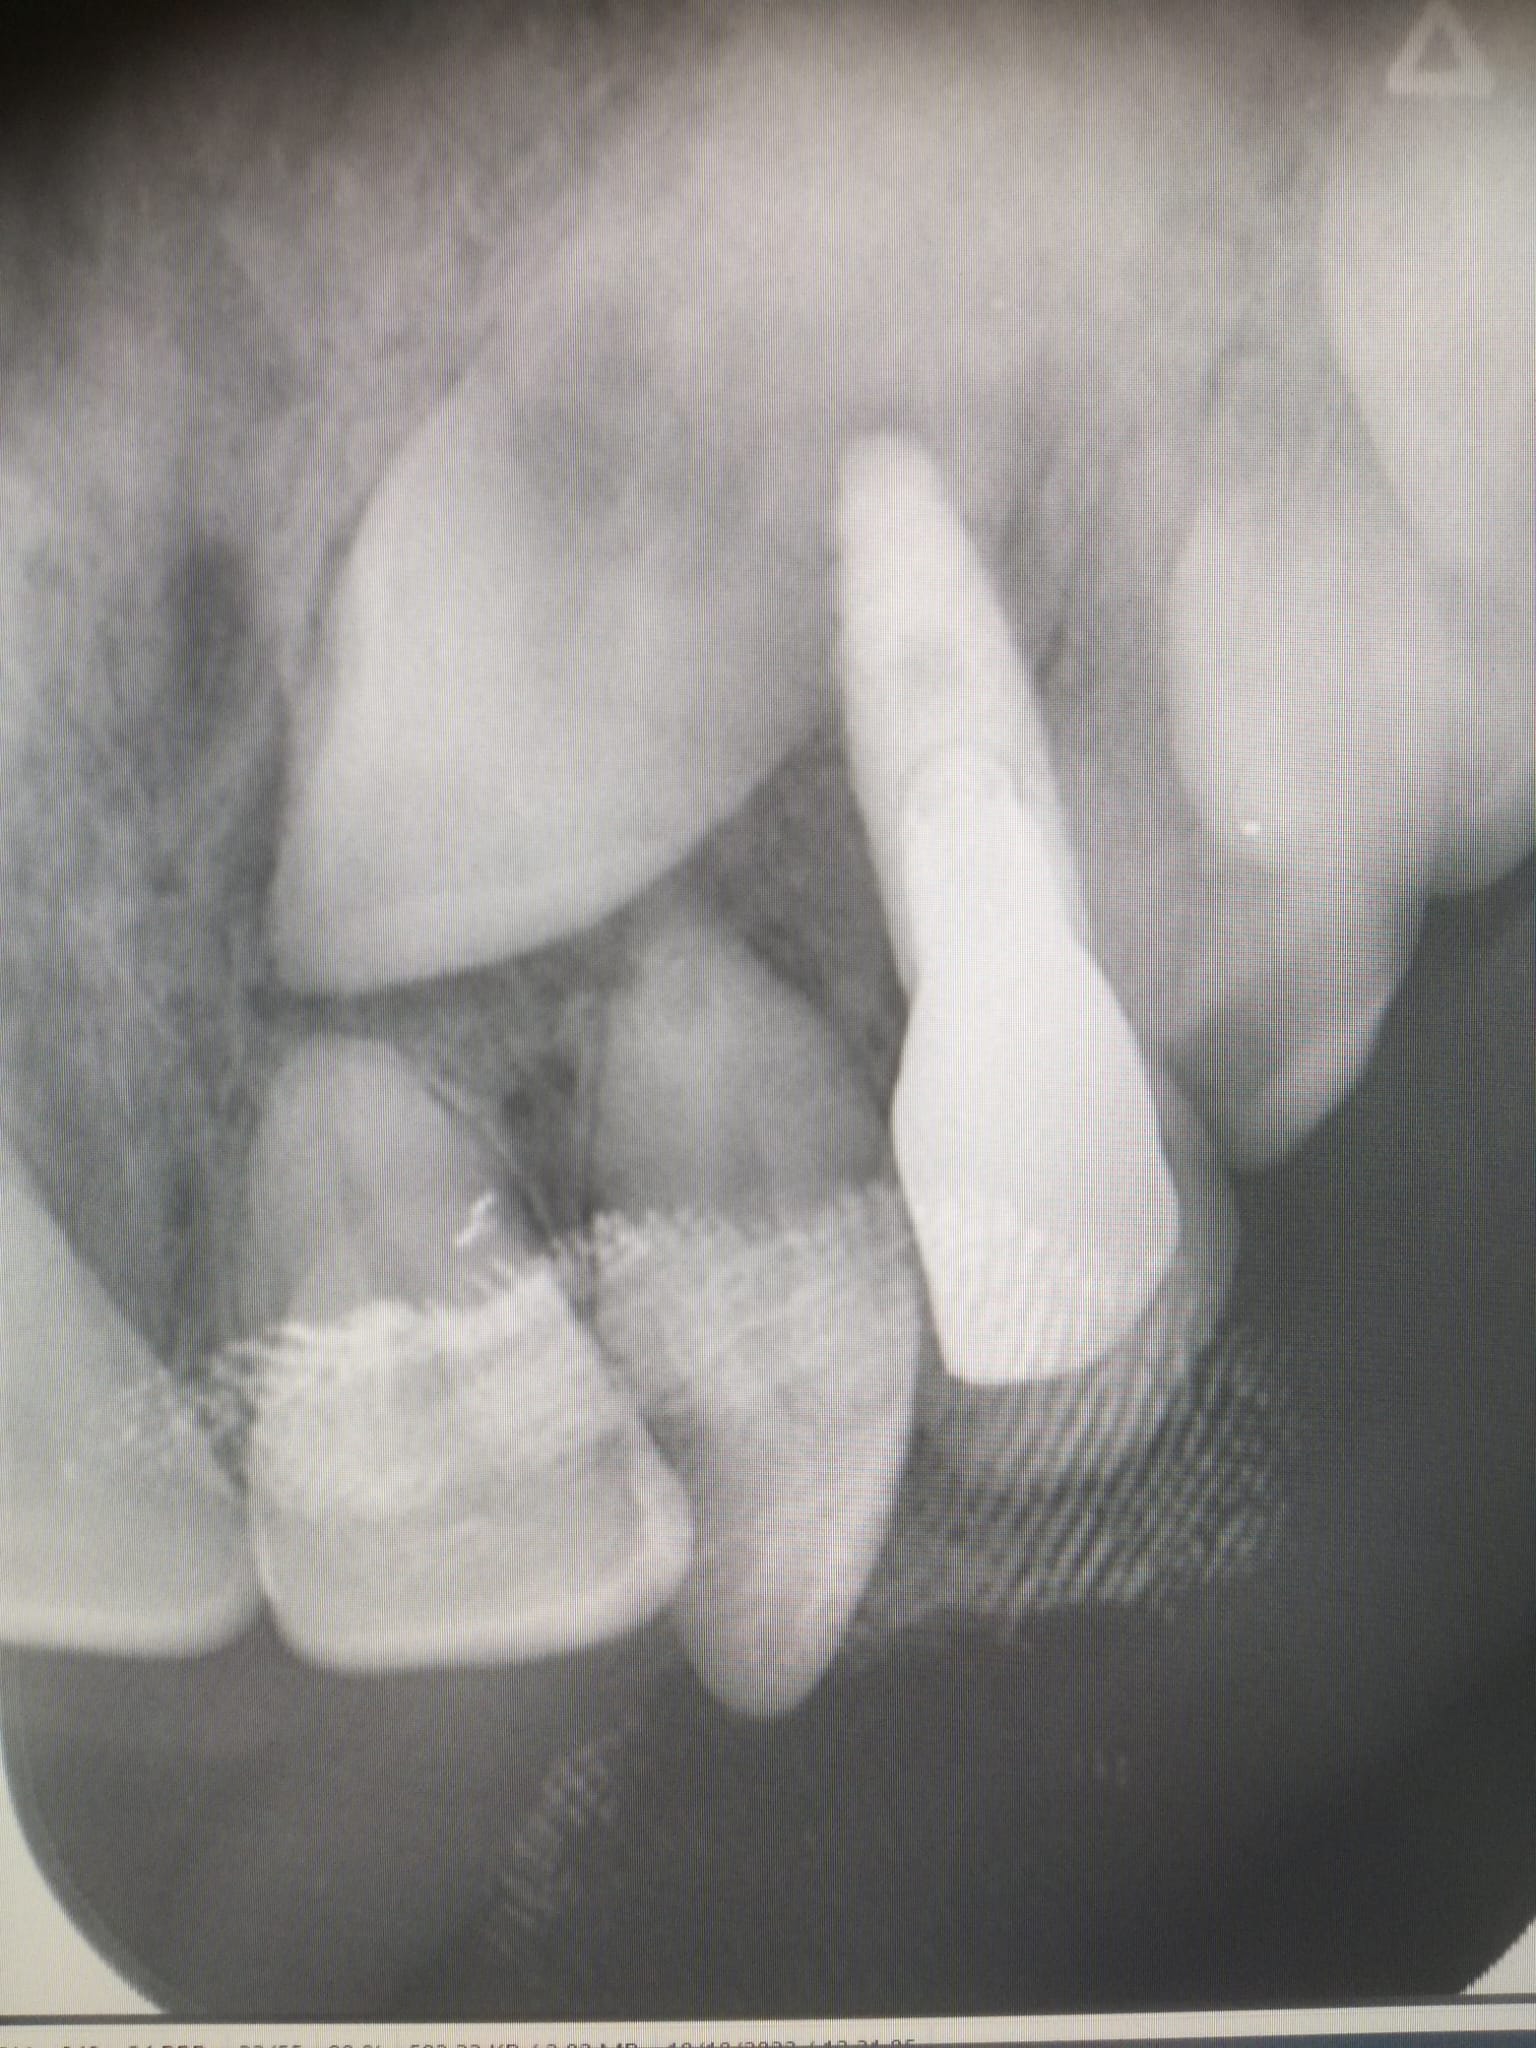

là par exemple on est très très proche de la racine... :

3b4kdca6bxig2am518lqpvuf47g3 - Eugenol

@ Hokusai

Là aussi on est très proche. Trop d'ailleurs.

Ca s'est mal terminé.

Je me souviens d'une conf à l'ADF d'un praticien qui affirmait avec beaucoup d'aplomb qu'il n'y avait aucun problème à transfixer des racines. Depuis j'ai vu ce cas, et j'ai un peu plus de doutes.

C’était juste un peu d’inquiétude de ma part comme je voyais un peu d’interrogation chez mon dentiste que le bout de la racine soit entre 0,5mm et 1mm de l’implant, j’essayais de me rassurer en me disant que la racine était dévitalisée et je pensais donc que ça pouvait marcher sans devoir tout recommencer 😔